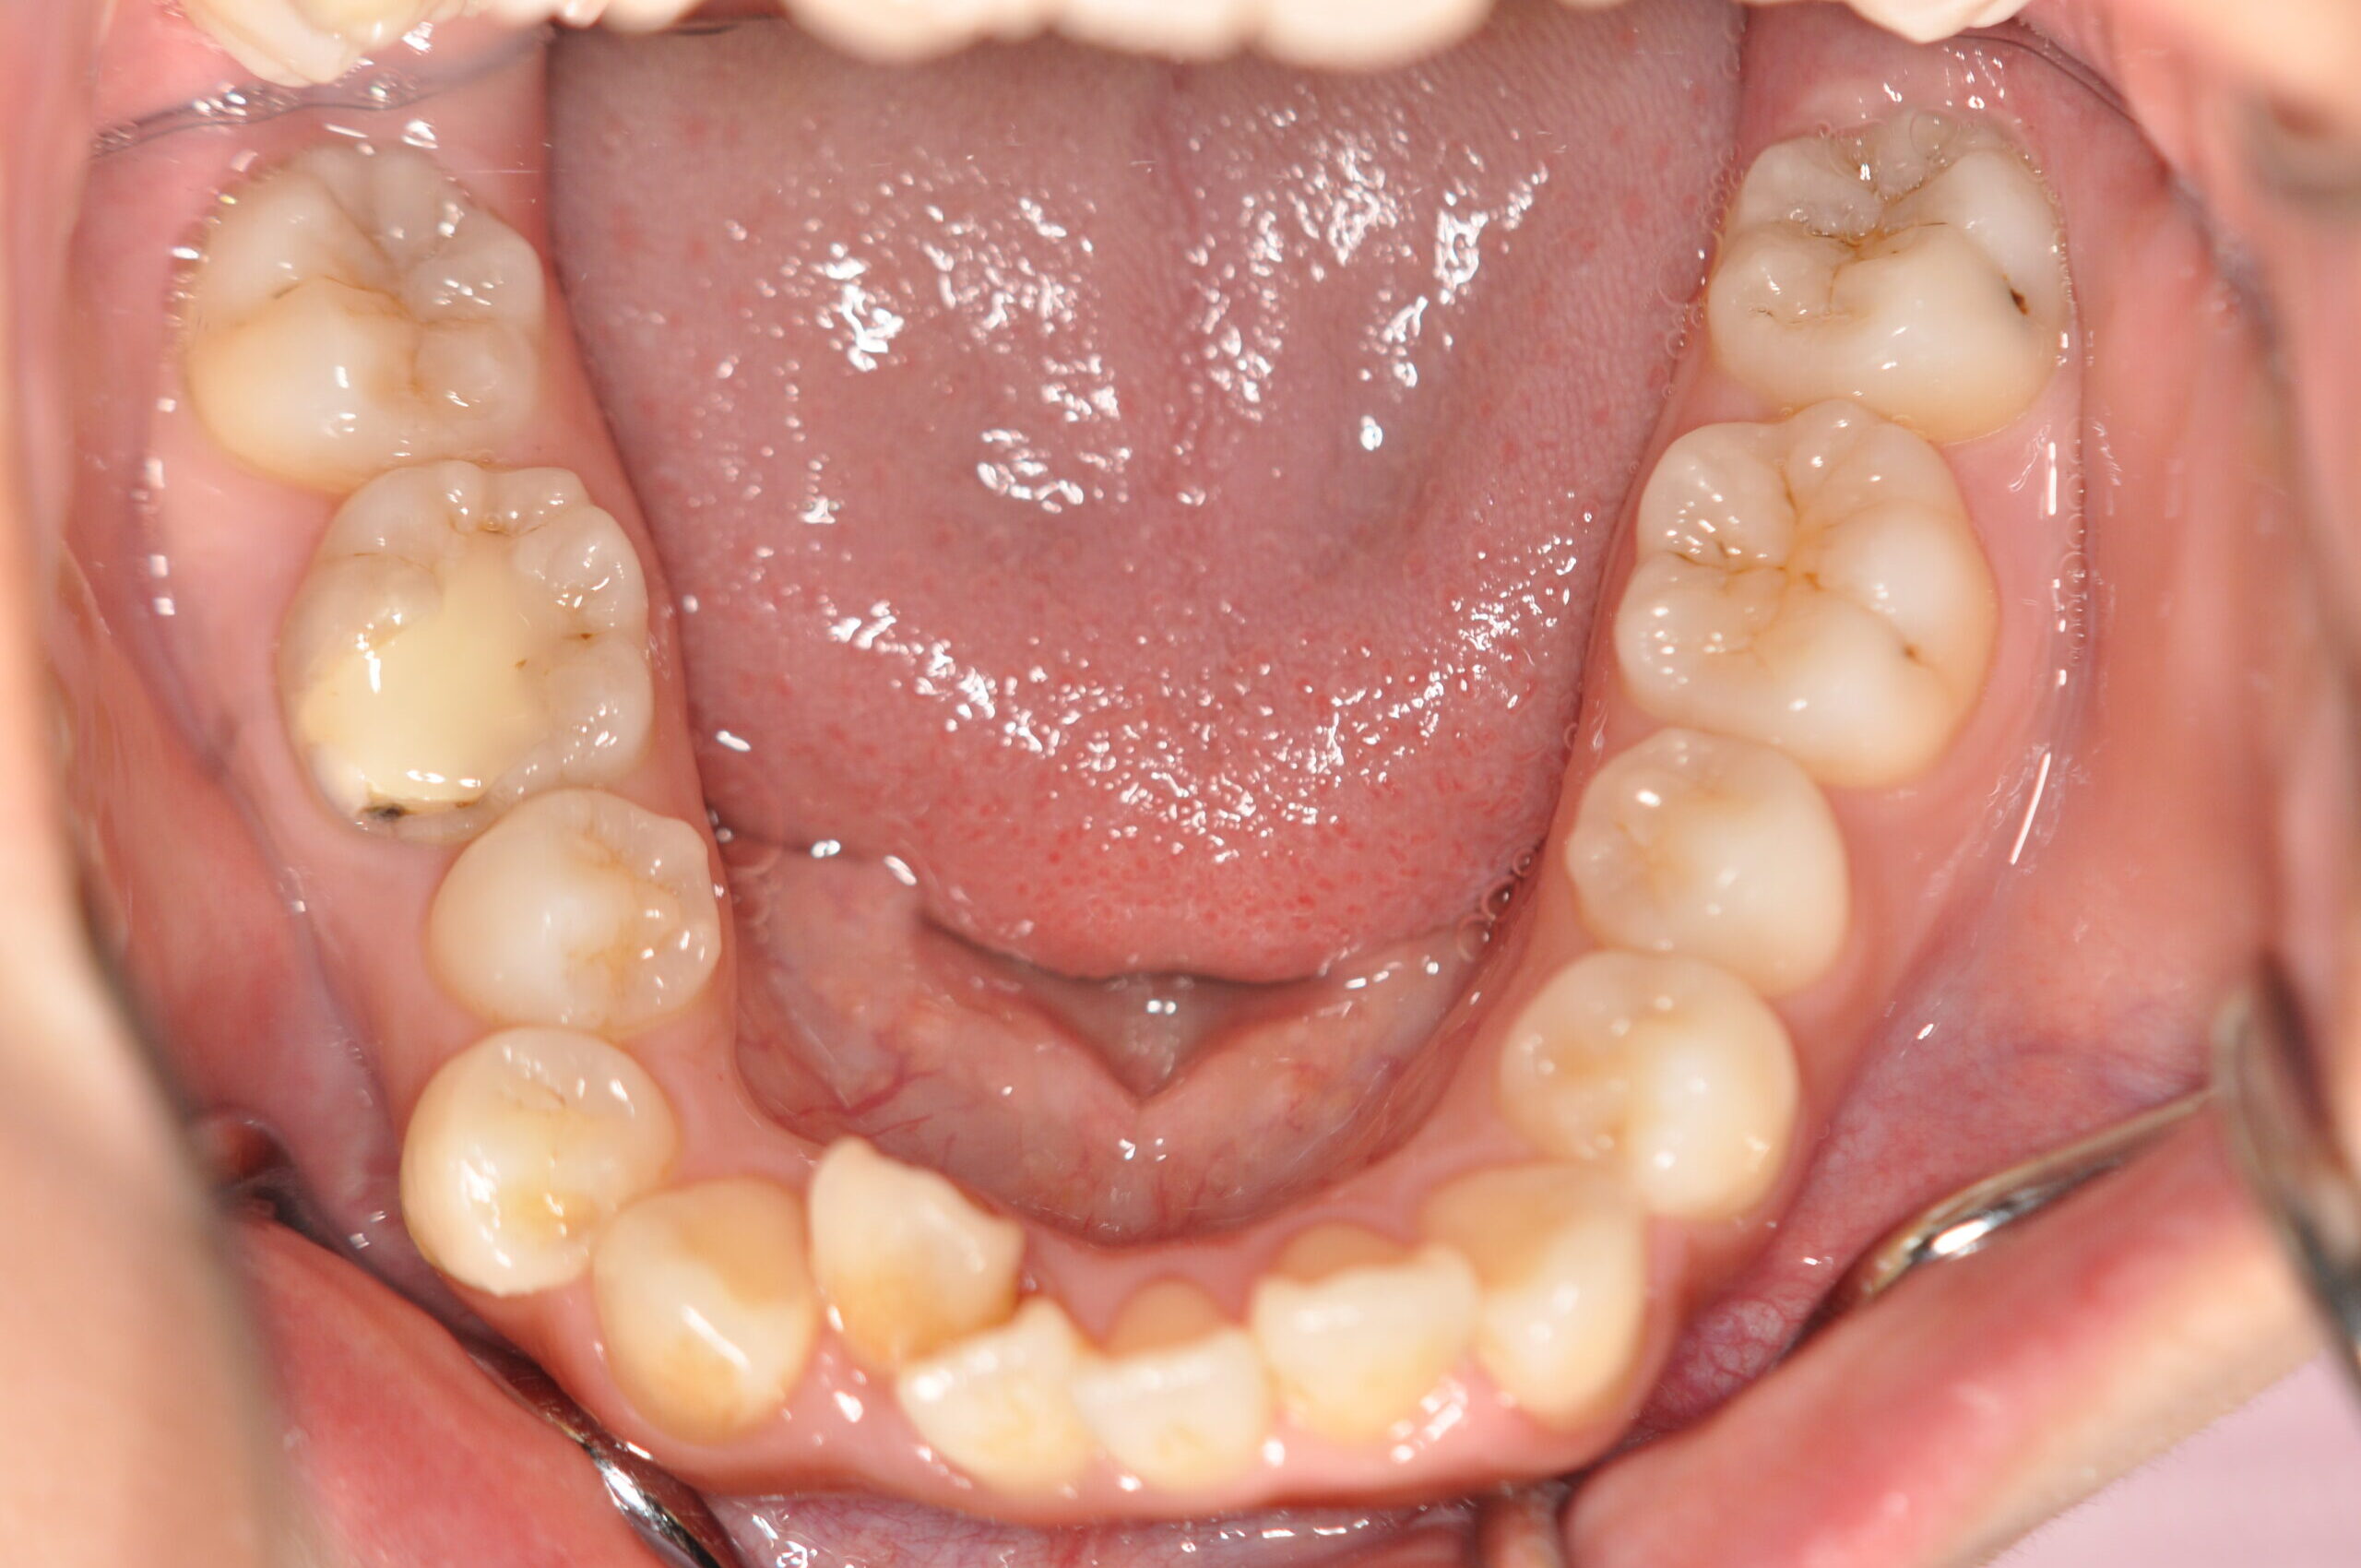

動的治療終了時

症例 症例 症例 症例